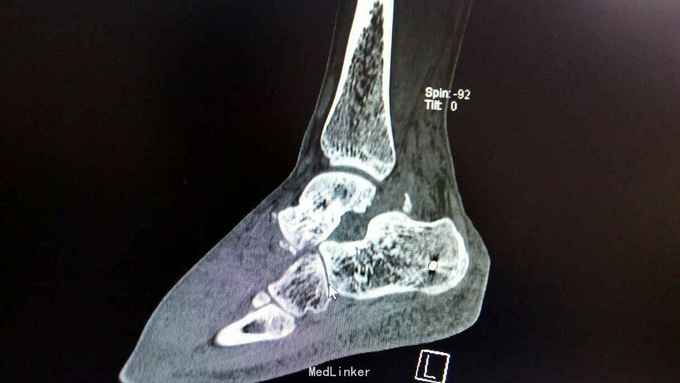

距骨骨折并脱位

重物砸伤左足疼痛畸形14小时。

左踝至中足肿胀,左足内翻畸形,皮肤可见少许细小水泡,压痛,足背动脉搏动可,足趾活动可,感麻木。

距骨骨折并脱位 入院行闭合手法复位失败,予以跟骨牵引5天,石膏外固定3天,皮肤水泡、肿胀消退后行,距骨骨折脱位切开复位内固定+距舟关节融合。术后支具外固定,勿负重3个月。